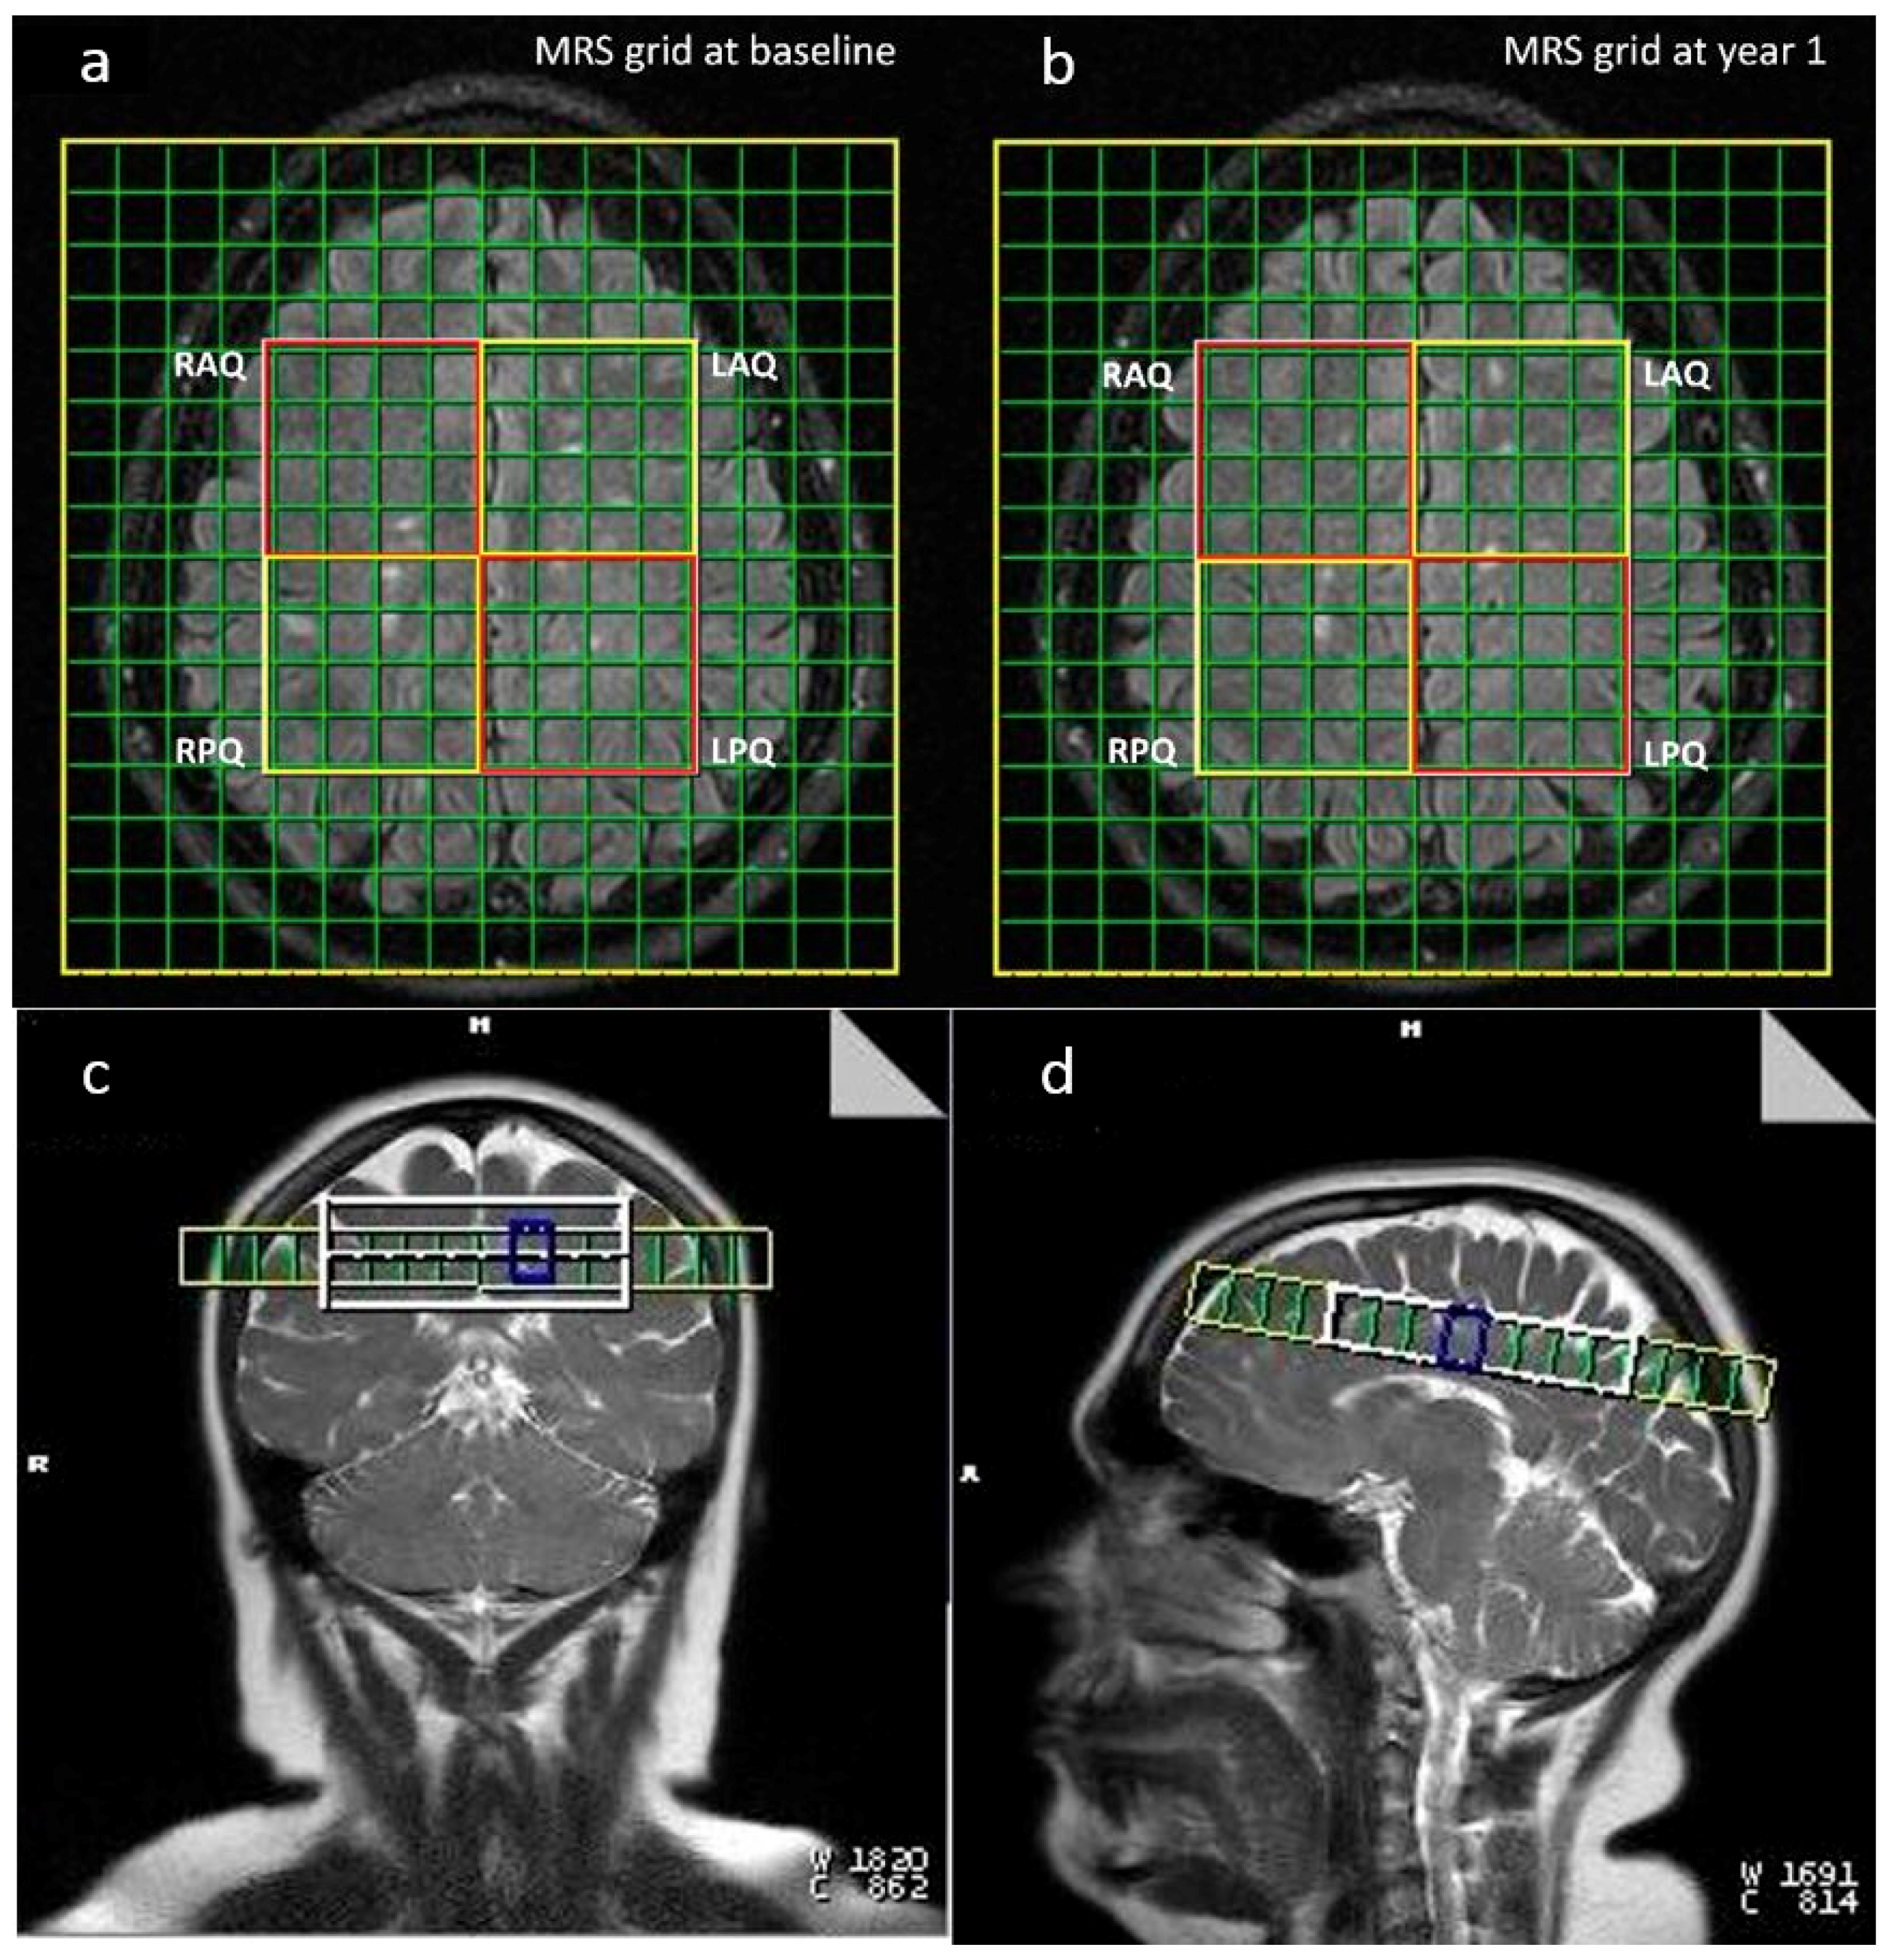

2.2. Image Acquisition

2.3. Image Processing